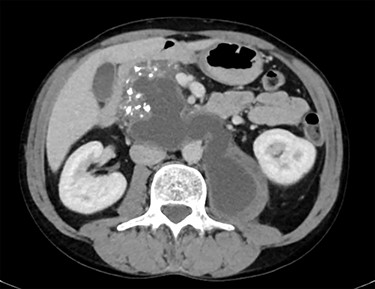

A 45-year-old man presented to his general practitioner complaining of 2 months of progressive left hip pain. Over the preceding 2 weeks he had been struggling to mobilize. His general practitioner (GP) investigated with a non-contrast computed tomography (CT) of the pelvis. This found a cystic lesion within the left psoas muscle with areas containing coarse calcification. The findings, overall, were suspicious of tumour, likely a teratoma. A CT chest, abdomen and pelvis with intravenous contrast was arranged. The pathology in the left psoas was found to represent a pancreatic pseudocyst extending from a heavily calcified pancreas, over the anterior aspects of the aorta and inferior vena cava (IVC) before reaching the left psoas muscle body (Figs 1 and 2). There were multiple other cystic regions noted within the pancreatic parenchyma and peripancreatic tissue. The patient was referred to the emergency department for surgical review.

CT showing calcified pancreas with pseudocyst extending from pancreas to left psoas muscle.